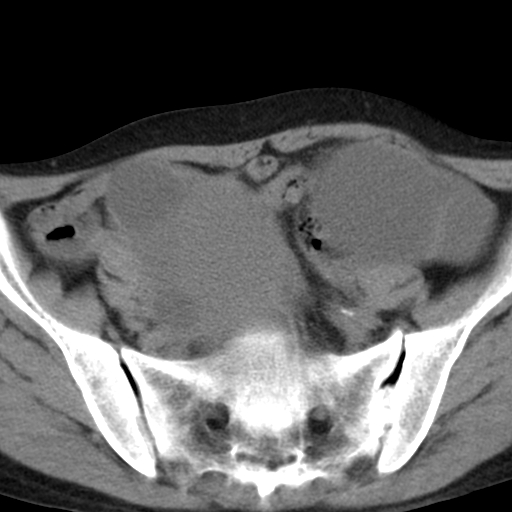

女,70,腹部间断性胀痛三月余

子宫宫腔及双侧附件积液,原因?

考虑卵巢囊腺瘤,不排除囊腺癌。

考虑卵巢囊腺瘤或囊腺癌。实质成分太多,考虑后者可能性大.

年龄较大还是恶性可能大,不排除库肯勃瘤

双侧卵巢粘液性囊腺癌,不多赘述。

考虑卵巢囊腺瘤;囊腺癌不能排除(理由:病人年龄较大,病灶外形欠规整、囊实相间,实性成分较多均支持囊腺癌)。要是能听听九目段老师的点评就好了!

考虑囊腺癌,子宫病变不能排除吧,建议mri检查。